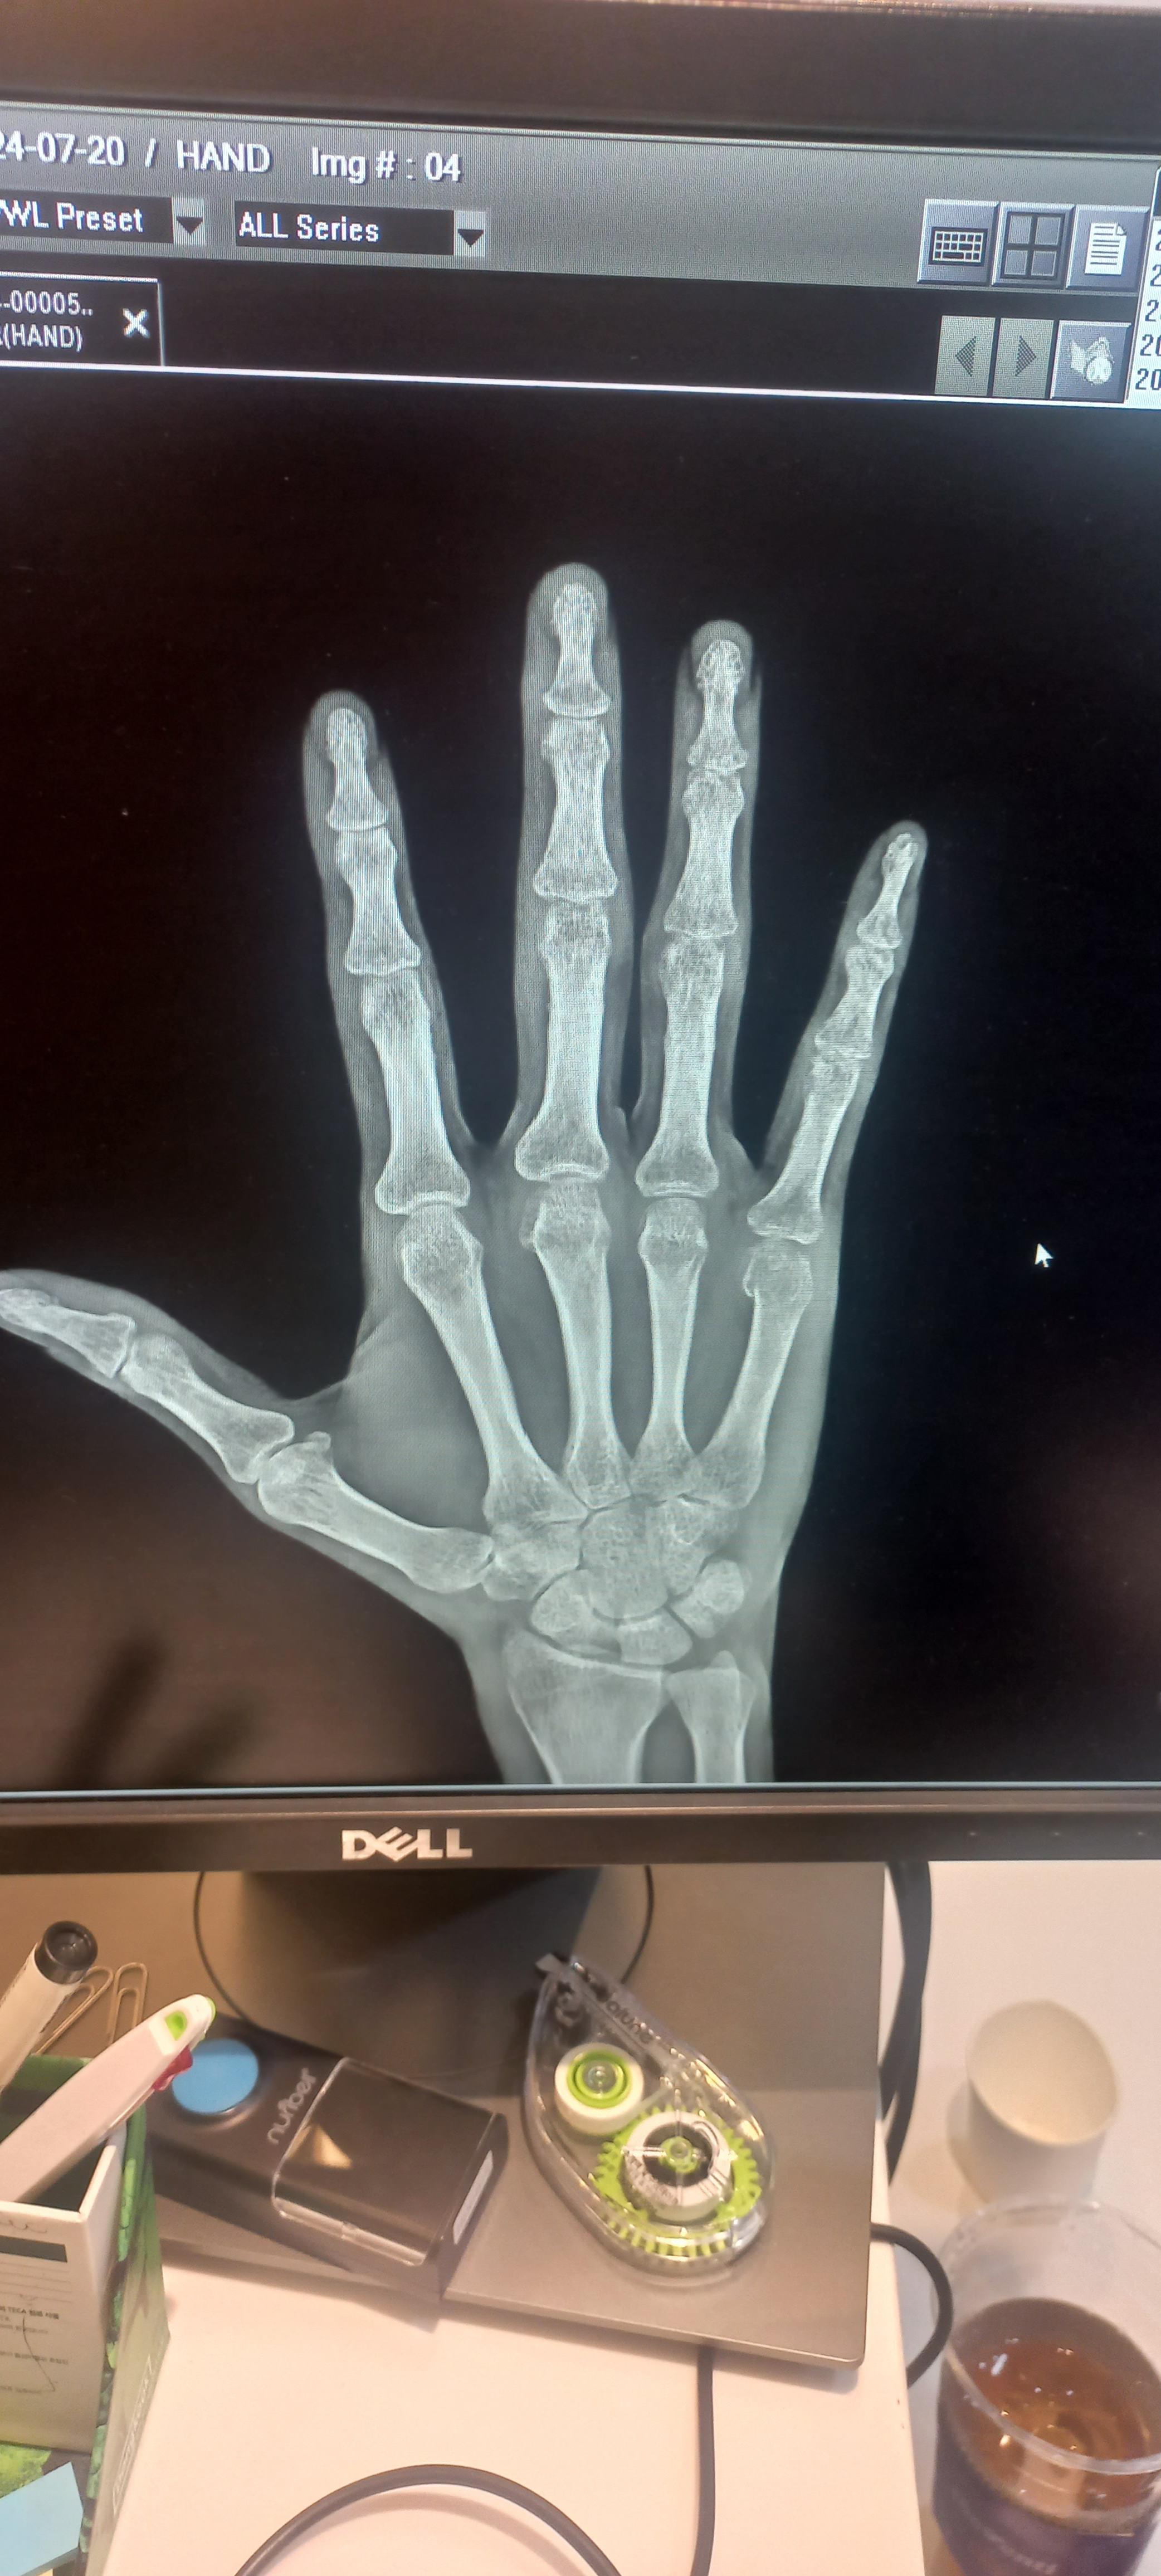

중수골 골절 재활 수술

얼마전에 중수골 골절을 당했어요. 화가 나서 주먹을 벽을 쳤죠. 그러니 부러졌죠. 새끼 손가락 뼈가 중수골이에요. 그래서 병원 치료를 했어요. 6주정도 기브스를 하는데요. 다른 병원은 수술을 요구 하기도 해요. 하지만 기브스로도 되더라구요. 수술은 핀을 박아요. 무섭죠. 그러니 병원 진료는 몇군데 가보세요. 그런후 결정하세요.

뼈는 시간이 지나면붙어요. 하지만 그 이후가 중요한데요. 기브스를 하면 뼈가 굳어요. 손가락이 굳어 버리죠. 저는 깜짝 놀랐어요. 손을 못쓰는 것이 아닌가 하구요. 그래서 열심히 재활을 했답니다. 주먹을 쥐었다. 피세요. 그것을 반복하죠. 이것을 꾸준히 하면 펴져요. 관절은 계속 운동하면 펴져요. 그러니 걱정마세요. 그리고 따뜻한 물에서 운동해도 좋아요. 그러면 효과가 좋아요. 유튜브에 손가락 재활운동을 쳐보세요. 많은 영상이 있어요.

결론적으로 말하면요. 중수골 골절을 당하면 정형외과를 가세요. 그리고 기브스 치료를 해요. 4주 정도 지나면 기브스를 풀게 되요. 그럼 주먹을 쥐었다 폈다 하세요. 그러면 관절을 풀어 집니다. 손가락이 굳는다고 놀라지 마세요. 일시적으로 굳어지는 건데요. 주먹을 취었다 폈다 하면 풀려요.